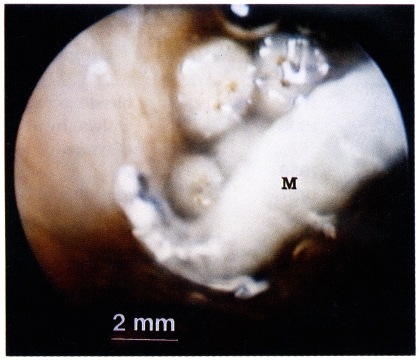

A 54-year-old male farmer visited the outpatient clinic of the Department of Otorhinolaryngology, Hallym University Hospital in August 16, 1996. He complained of blood tinged discharge and tinnitus for two days. Otoscopic examination revealed a number of maggots, blood tinged discharges, and cerumen in the left external auditory canal (

Fig. 1). The external auditory canal showed no hyperemic inflammation and tympanic membrane was intact. There were no maggots or lesions in the right external auditory canal. Maggots were removed under the light microscopic field. The external auditory canal was washed with ether to anesthesize worms. There were no maggots or any discharge in the following examinations in one and three weeks. He no longer complained of tinnitus after treatment.

Fig. 1

Lucilia sericata maggot (M) in the left external auditory canal of the male farmer seen via otoscope.